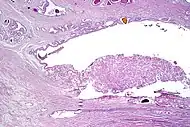

- Multiple nucleoli

- Eccentric nucleoli[4]

Acinar adenocarcinoma with multiple nucleoli.

Acinar adenocarcinoma with double and eccentric nucleoli.